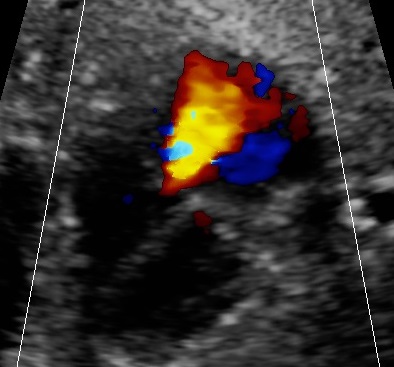

- holosystolic tricuspid insufficiency

- Thyroid circumference and in case of goiter the vascularisation of the thyroid

- signs of heart-insufficiency, like tricuspid valve insufficiency or ascites.1,2,6,8,9,10

Our patient presented with an otherwise unexplained, persistent fetal tachycardia some years after radioactive iodine treatment for Grave’s disease. The fetus presented tricuspid insufficiency as a sign of beginning heart failure. The neonate was treated with b-blockers and thiamazole, the mother was allowed to breastfeed and the outcome was excellent.